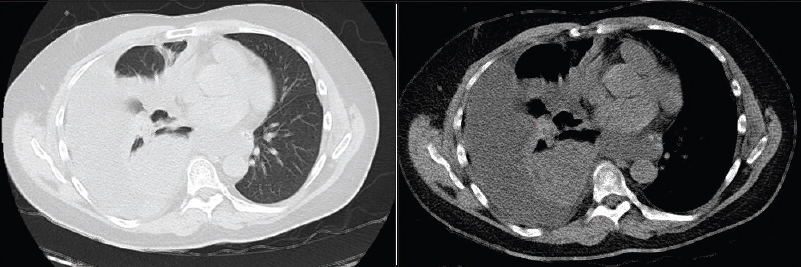

Sur la radio de thorax, le médiastin est repoussé par l’opacité, il est donc comprimé par un épanchement pleural.

Dans le cas d’une atélectasie le médiastin aurait été attiré vers l’opacité.

L’angioscanner thoracique est l’examen de choix pour éliminer une embolie pulmonaire, ici, il permettra de plus d’explorer l’étiologie de la pleurésie.

Vous recevez les images clés du scanner thoracique. Mme F. est hospitalisée. Elle a été bien soulagée par la ponction pleurale. Vous organisez une fibroscopie bronchique qui retrouve un adénocarcinome bronchique TTF1+, envahissant la bronche intermédiaire droite.